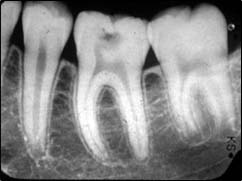

Rétroalvéolaire

Il s’agit de radios de petites tailles placées et orientées dans votre bouche et ciblant un secteur de une à trois dents. Elles permettent une vision plus précise de certains détails.